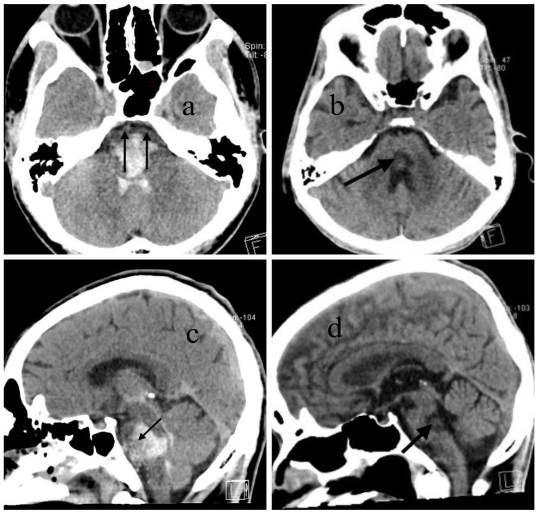

Follow-up CT or MRI was performed in the 3rd-4th week to exclude underlying lesions such as vascular malformations or tumors. The mRS was used to evaluate outcomes at week 4 and month 6. Special attention was given to anterior pontine involvement on initial CT scans. The hypothesis is complete involvement of the anterior pons was associated with poor recovery (vegetative state), while partial sparing correlated with better outcomes.

All 14 patients received comprehensive stroke care, including: strict blood pressure control (target SBP 140 mmHg), stabilization of vital signs, aggressive management of infections, ventricular drainage when obstructive hydrocephalus was present, early tracheostomy, prompt management of complications. Three patients died during hospitalization due to cardiac arrest associated with atrial fibrillation and failed resuscitation. Two patients with end-stage renal disease (ESRD) died from volume overload and related complications within the first week. Two surviving patients, who had complete ventral pons involvement, remained in long-term vegetative state despite aggressive treatment and absence of major comorbidities. Seven patients demonstrated partial sparing of the anterior pons on CT. These patients showed improvement in consciousness by week 4, responding to simple commands, and achieved partial functional independence by month 6. At 6 months: all 7 patients were able to communicate effectively. Motor recovery varied: some could ambulate with an ataxic gait, others required a wheelchair for mobility. All required daily assistance for activities of living.

Anatomically, the corticospinal tracts responsible for voluntary motor control are arranged ventromedial to dorsolateral within the pontine basis. In contrast, the cranial nerve nuclei and reticular formation, which control functions such as arousal, autonomic regulation, and coordination, are mainly located in the dorsal pons (tegmentum). When the hematoma completely involves the ventral pons, the corticospinal tracts are severely damaged, often leading to long-term motor deficits or a vegetative state, as seen in two patients in our series. However, when partial sparing of the ventral pons is present, as in seven of our cases, patients showed recovery of consciousness and meaningful motor function over time. These findings suggest that the most anterior part of the pons, which contains the corticospinal tract, is a critical region for predicting long-term outcomes in terms of motor coordination and the severity of motor deficits.

Our treatment decision framework is designed to assist emergency physicians and general practitioners who often face the responsibility of guiding patients families at the time of diagnosis. It integrates clinical and radiological criteria to determine the feasibility of active treatment. While massive ventral PPH generally carries a poor prognosis, our findings show that not all such cases result in death or vegetative state. Patients with no severe comorbidities and partial sparing of the anterior pons had a better-than-expected outcome, achieving communication, mobility with assistance, and some degree of independence.

Massive primary pontine hemorrhage is commonly associated with a poor prognosis. However, our case series demonstrates that functional recovery is possible in select patients. Specifically: Patients with partial sparing of the anterior ventral pons, and no severe comorbidities, showed significantly better outcomes than predicted. Total anterior pons involvement was associated with persistent vegetative state, even in otherwise healthy individuals. Further studies with larger sample sizes and prospective design are needed to validate these findings and refine the proposed decision-making framework.